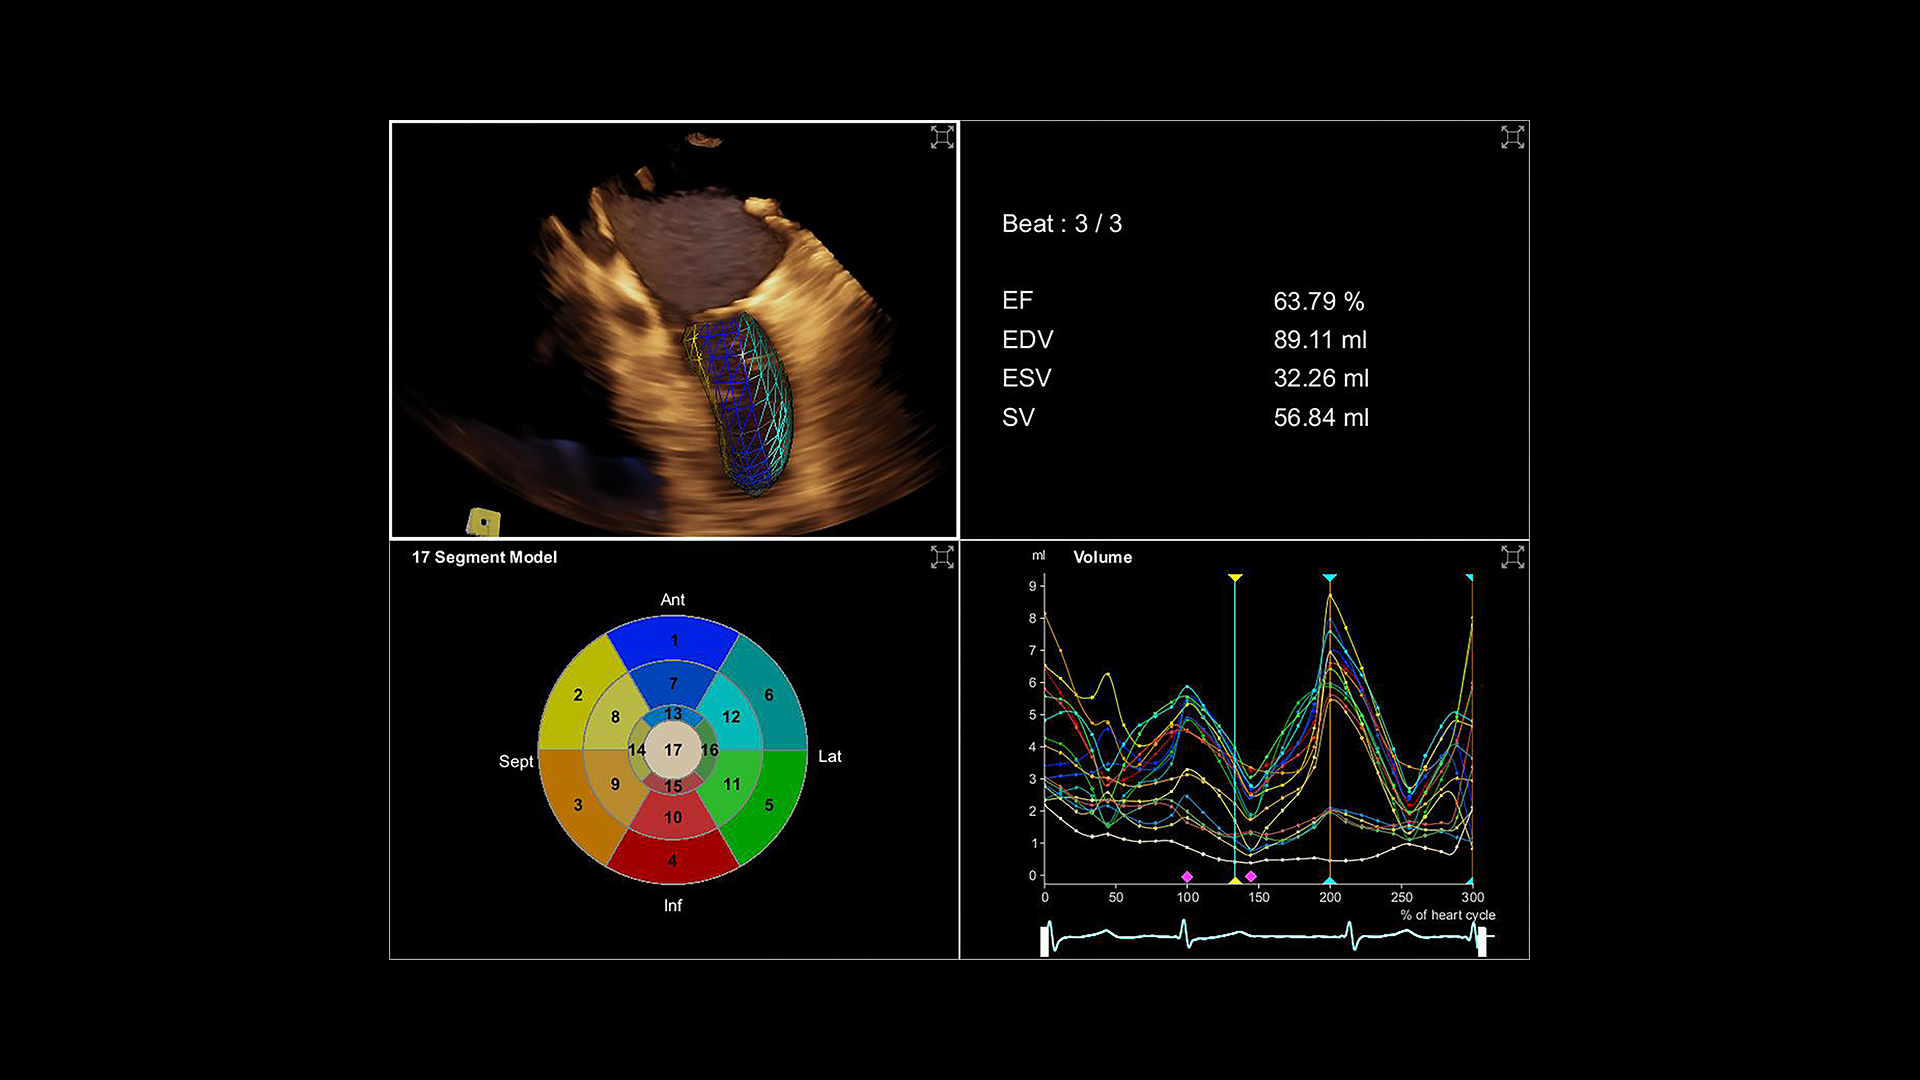

Slide-3_1-3D-LVA

eSie Left Heart

eSie Left Heart identifies and automatically contours the left ventricle and left atrium while improving consistency and reproducibility of left ventricular and left atrial quantification.